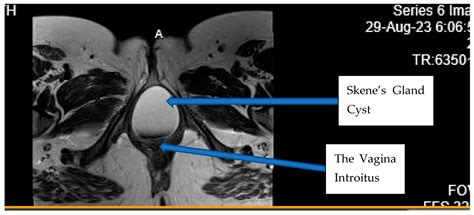

• Imaging Tests: Ultrasound or magnetic resonance imaging (MRI) may be used to confirm the diagnosis and determine the size and location of the cyst.

• skene duct cyst radiopaedia

• skene gland cyst